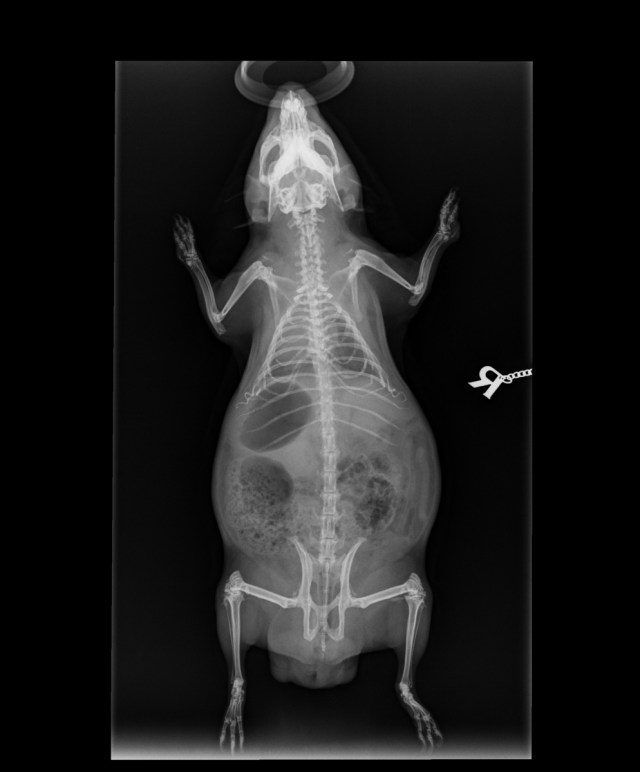

We showed you Neville’s x-rays on the A to Z in 2022; you can see those here in detail, especially at the top of the page — it’s easy to see his round bladder stones between his hip and his spine (high up in his bladder).

My ribcage is okay where it is bone, but where it is cartilage it looks unusual. In the top picture, at the bottom of the rib cage, about level with the bottom of the letter R (for right), you can see some curly things. Those should be straight, and curve back towards my ribs like the ones above! Dr Rebekah reckons that they didn’t develop properly before I was born, and the next image gives more clues.

It’s not easy to see those floating rib cartilages in this view, but you can tell they don’t join up below. And if you compare it with Neville’s you might see why.

If you follow Neville’s breast bone down, it ends in a bone which takes the line of the others. Now look at mine. It points down!

Mummy knew very early on that I had a lump under my chest and she asked Dr Rebekah about it, who said it was just my breastbone. It’s out of place, and not supported by those twirly cartilages at all. Dr R said I probably was a big baby, too big for my young mum, who had already had two girls just before she started growing me. So I didnt quite grow fully, or at least got a little squished.